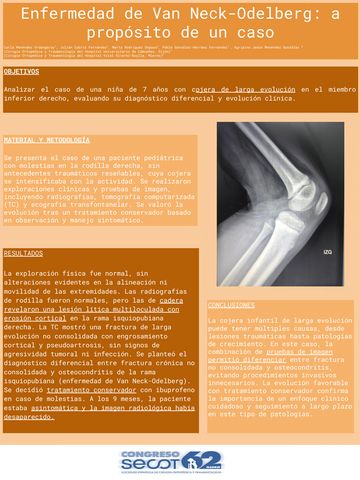

Enfermedad de Van Neck-Odelberg: a propósito de un caso

CARLA MENÉNDEZ URDANGARAY, JULIÁN CABRIA FERNÁNDEZ, MARTA RODRÍGUEZ DOPAZO, PABLO GONZÁLEZ-HERRÁEZ FERNÁNDEZ, JESÚS MENÉNDEZ GONZÁLEZ